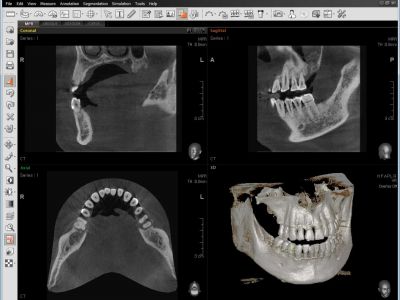

UNA TOMA, DOS IMÁGENES

Un escaneo con Smart Plus no solamente le brinda una imagen CT, sino también una imagen Auto Pano.

Esto significa que los pacientes que requieran ambas imágenes no se sometan a dos radiografías. Ambas imágenes CT y Auto Pano se muestran dentro de la función Over View